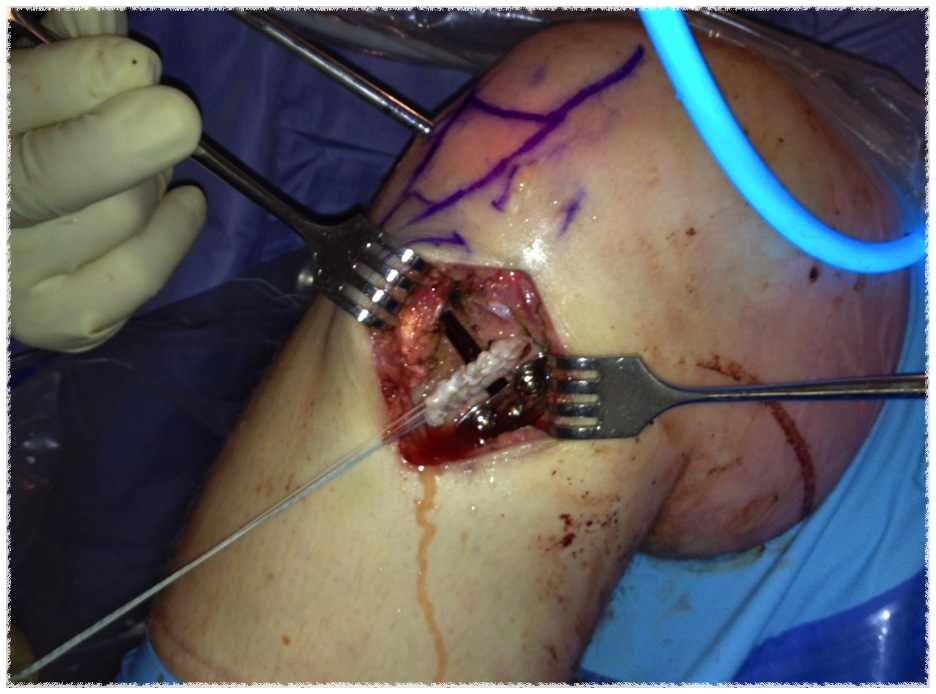

Technique

- medial opening wedge with plate and allograft bone

ACL + High tibial osteotomy for ACL + chronic posterolateral corner

ACL / Posterolateral corner / patient in varus

ACL + high tibial osteotomy